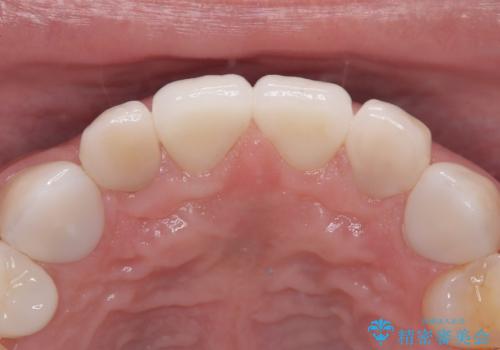

【セラミッククラウン】他院で治療したセラミッククラウンをやりかえたい

- 他院で1年ほど前にセラミッククラウンを入れたそうですが、しばらくしてから歯茎から膿が出てきたそうです。

歯髄診にて歯髄が失活していることが判明したため、クラウンを除去し根管治療を行ってから、再度オールセラミッククラウンを作成しています。

今回のケースはクラウン除去した際に露髄点は認められなかったため、形成時の発熱が原因であったと推測しています。